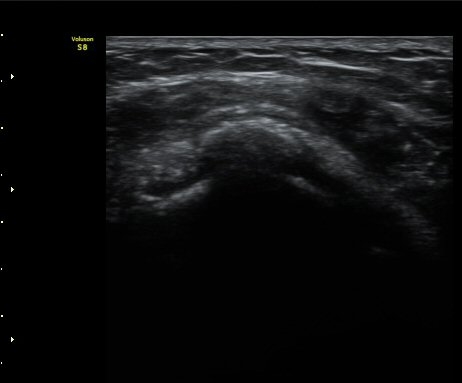

±Ø»ó°Ç Á¾´Ü¸é°Ë»ç½Ã ±Ø»ó°ÇÀÇ Ç¥Ãþ¿¡¼­ °üÂûµÇ´Â °ßºÀ¿À±¸µ¹±â Ⱦ´Ü¸é°Ë»ç»ó¿¡¼­

ÀδëÀÇ ºñÈİ¡ °üÂûµÈ´Ù(»çÁø 4). ±Ø»ê°ÇÀÇ Á¾´Ü¸é°Ë»ç¿Í Ⱦ´Ü¸é°Ë»ç¿¡¼­ ±Ø»ê°Ç ½ÉÃþ¿¡

Àú¿¡ÄÚ º´º¯ÀÌ °üÂûµÈ´Ù(»çÁø 5, 6).